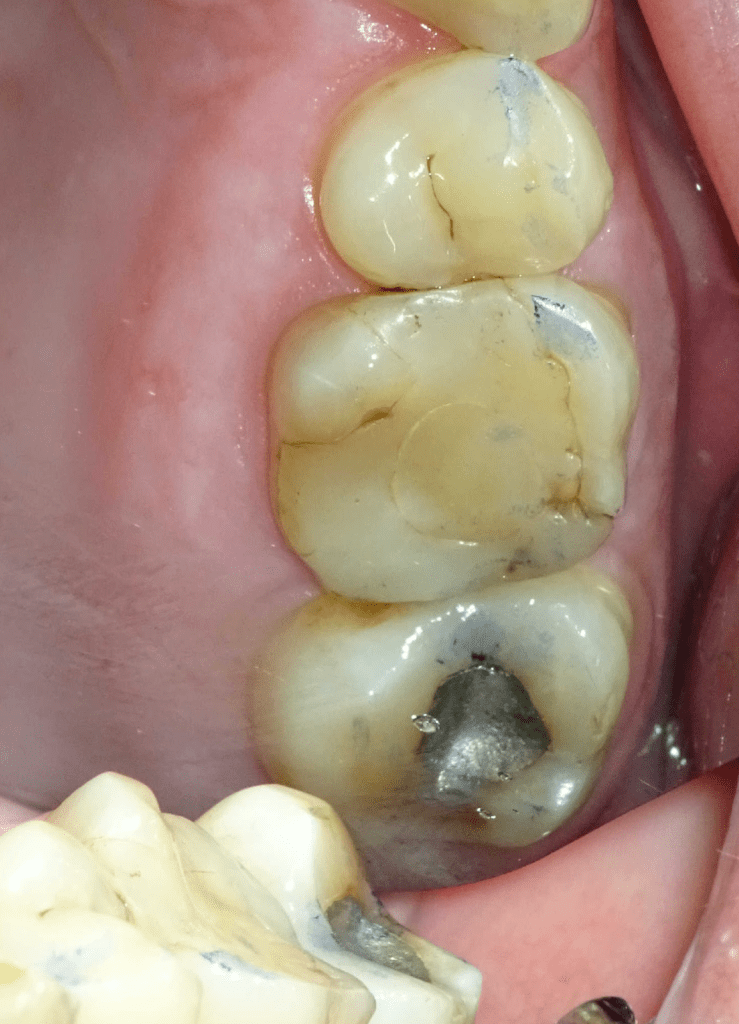

Fisura, remoción amalgama para explorar